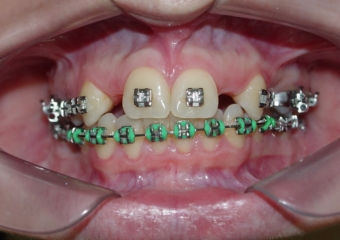

Imagem após extrações de dentes decíduos e instalação de um implante